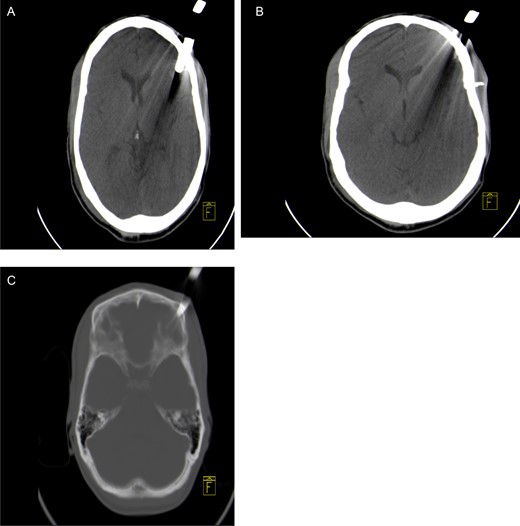

A 30-year–old male patient was stabbed in the head with a garden fork following a dispute with a neighbour. He was initially assessed at his local hospital, which referred him to our neurosurgery unit for further management. On arrival, he was haemodynamically stable and was noted to have a retained garden fork in the left frontal area. His Glasgow Coma Scale (GCS) was 14/15, with no associated neurological deficits. He was noted to have left peri-orbital swelling, but vision was intact. There was no active bleeding from the wound and no other associated injuries. He was intoxicated at the time of examination and had a generalized tonic–clonic seizure in the emergency department, which was aborted. He was loaded with phenytoin and put on maintenance therapy. A computerized tomographic (CT) scan of the brain showed a retained garden fork in the frontal area (Fig. 1). The garden fork prong had penetrated the left frontal cortex; however, it caused a lot of artefact making visualization of parenchymal tissue damage difficult to appreciate (Fig. 2). Tetanus toxoid was administered and he was taken to the operating theatre for removal of the garden fork under general anaesthesia. At induction, intravenous first-generation cephalosporin and metronidazole were administered for prophylaxis.

CT scout view showing a retained garden fork in the frontal area.